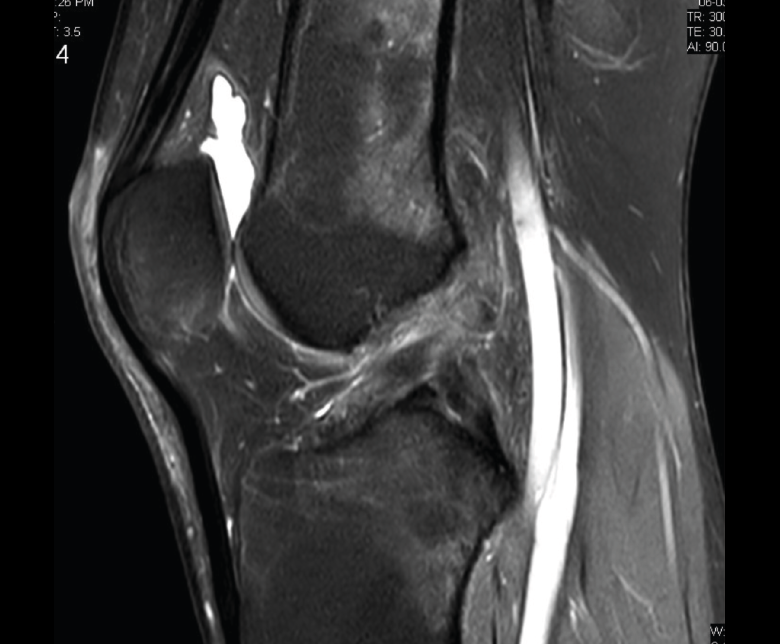

1.2.3. Ligamento cruzado posterior (LCP) (Figuras 45 y 46)

Figura 45. Corte de secuencia sagital T2 Fat-Sat de resonancia magnética: ligamento cruzado posterior normal.

Figura 46. Corte de secuencia sagital T2 Fat-Sat de resonancia magnética: rotura de ligamento cruzado posterior distal.